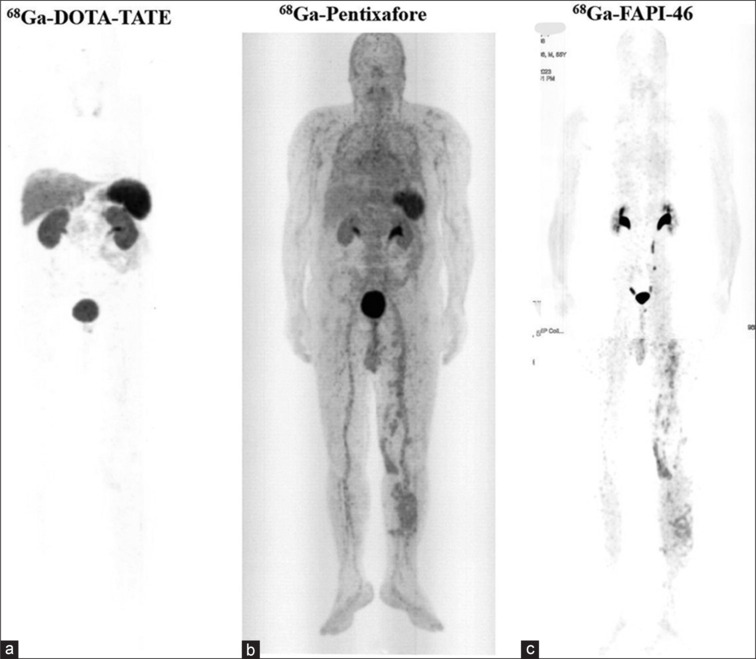

一位55岁男性晚期恶性黑色素瘤患者接受了手术、放疗和化疗。尽管进行了这些治疗,[18F]FDG PET/CT显示疾病进展明显。使用镓-68示踪剂对CXCR4、SSTR2和FAP进行靶向成像,确定了个性化治疗的生物标志物。这导致了[177Lu]Lu-FAPI-2286的选择。在第一个周期后,患者报告疼痛缓解,但随后的影像学显示快速脑转移。这个病例强调了个性化医疗和分子成像在治疗晚期黑色素瘤中的重要性。

A 55-year-old male with advanced malignant melanoma received surgery, radiotherapy, and chemotherapy. Despite these treatments, [18F]FDG PET/CT showed significant disease progression. Targeted imaging with gallium-68 radiotracers for CXCR4, SSTR2, and FAP identified biomarkers for personalized therapy. This led to the choice of [177Lu]Lu-FAPI-2286. After the first cycle, the patient reported pain relief, but subsequent imaging revealed rapid brain metastasis. This case highlights the importance of personalized medicine and molecular imaging in treating advanced melanoma.